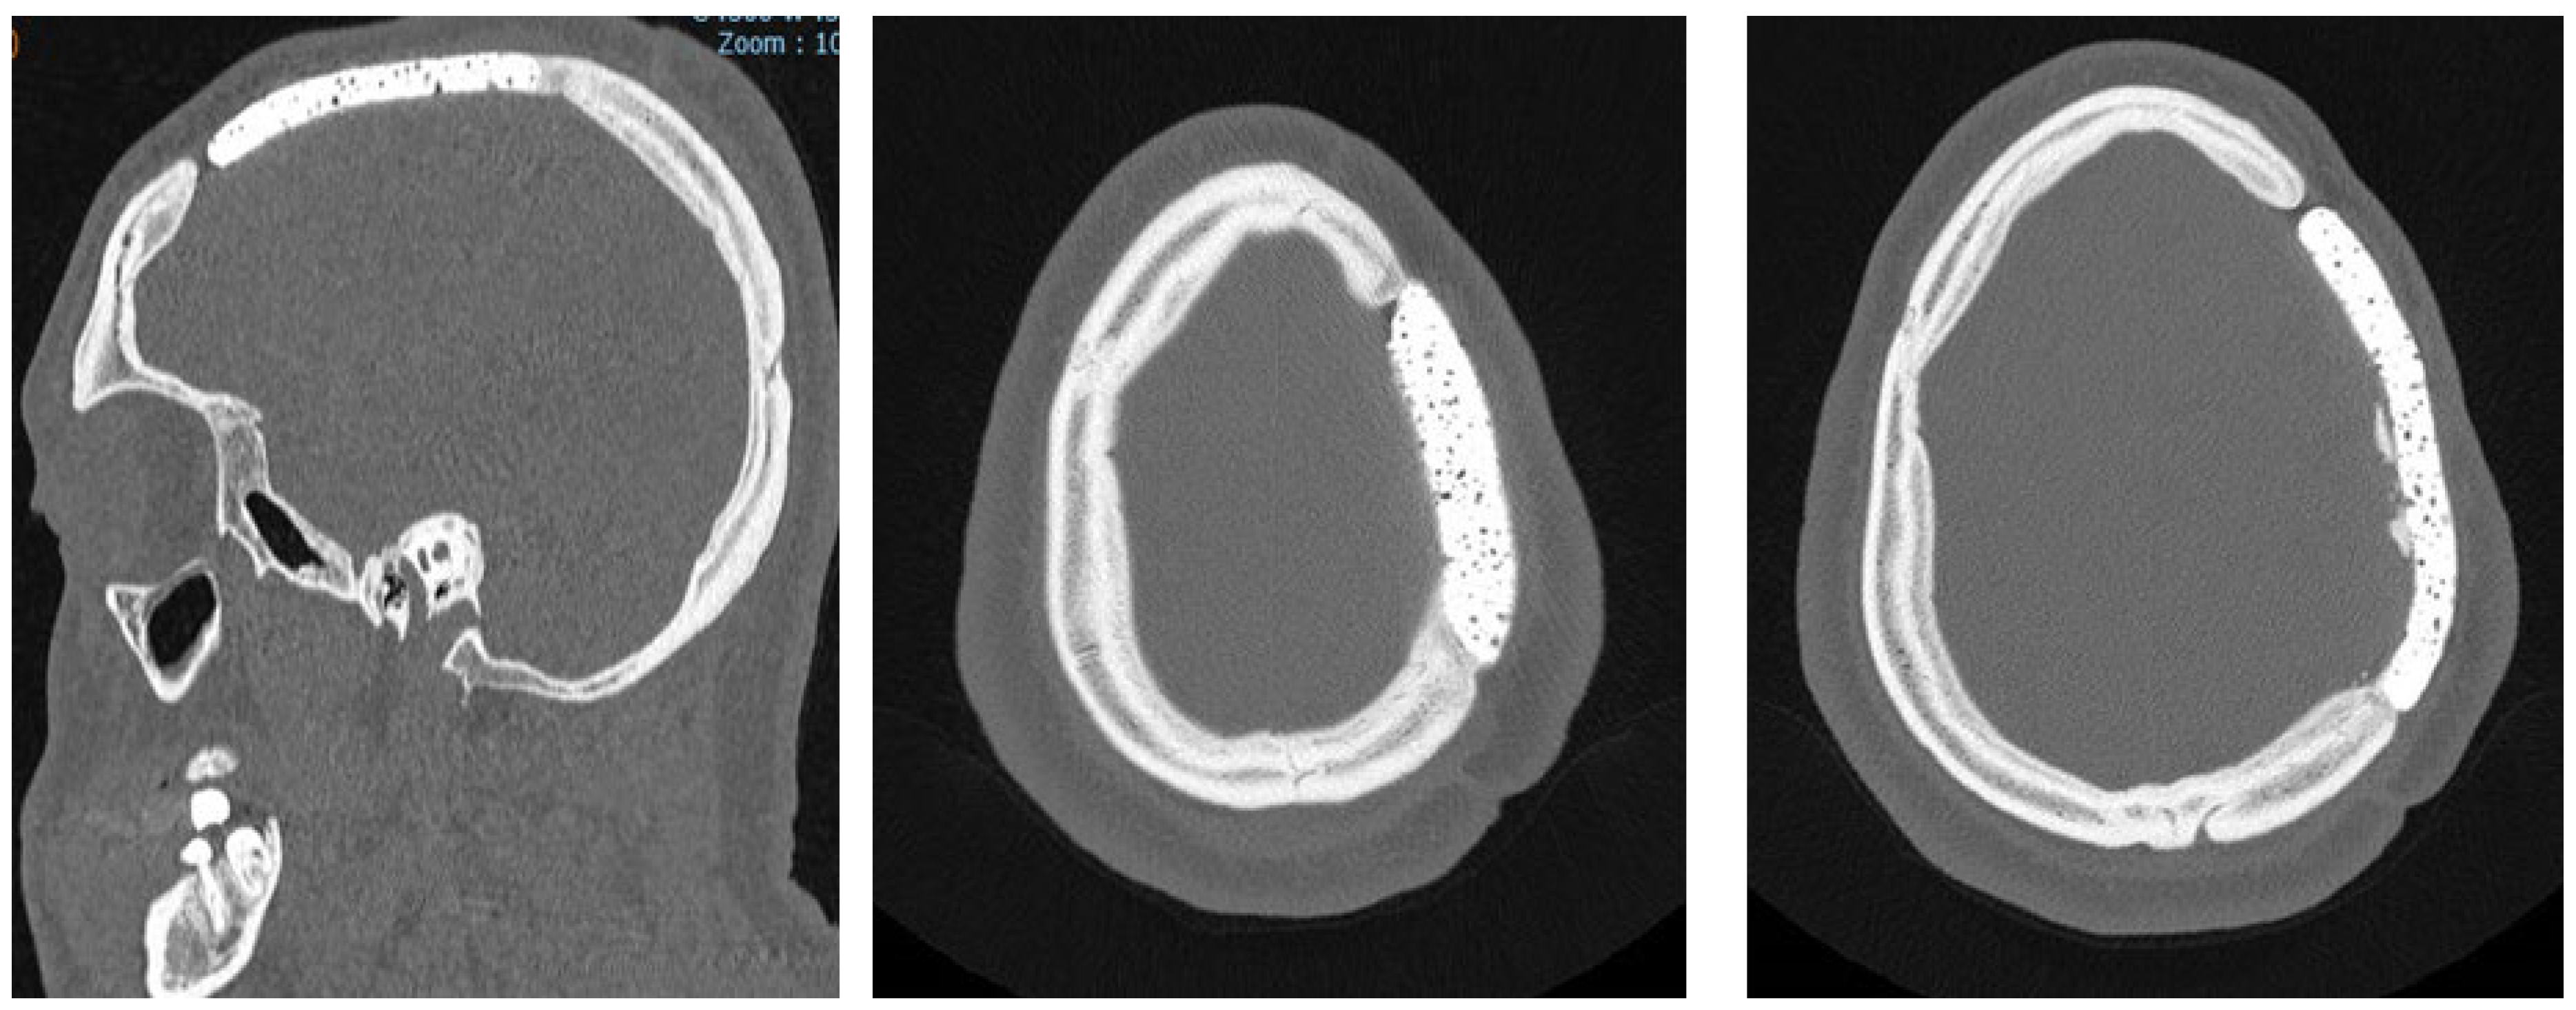

Figure 2. Bone CT-scan at 48h post-operatively: (a) axial bone CT image showing satisfactory placement of the cranioplasty flap; (b) 3D reconstruction of the CT scan.

The postoperative course was uneventful in all cases, with no instances of acute complications such as wound dehiscence, infection, hematoma, or cerebrospinal fluid leakage. Immediate postoperative CT scans confirmed correct prosthesis positioning, with no evidence of displacement or misalignment in all cases (Figure 2a).

Radiological assessments, while performed, demonstrated progressive osseointegration, with bone remodeling visible at the prosthesis margins (Figure 5).